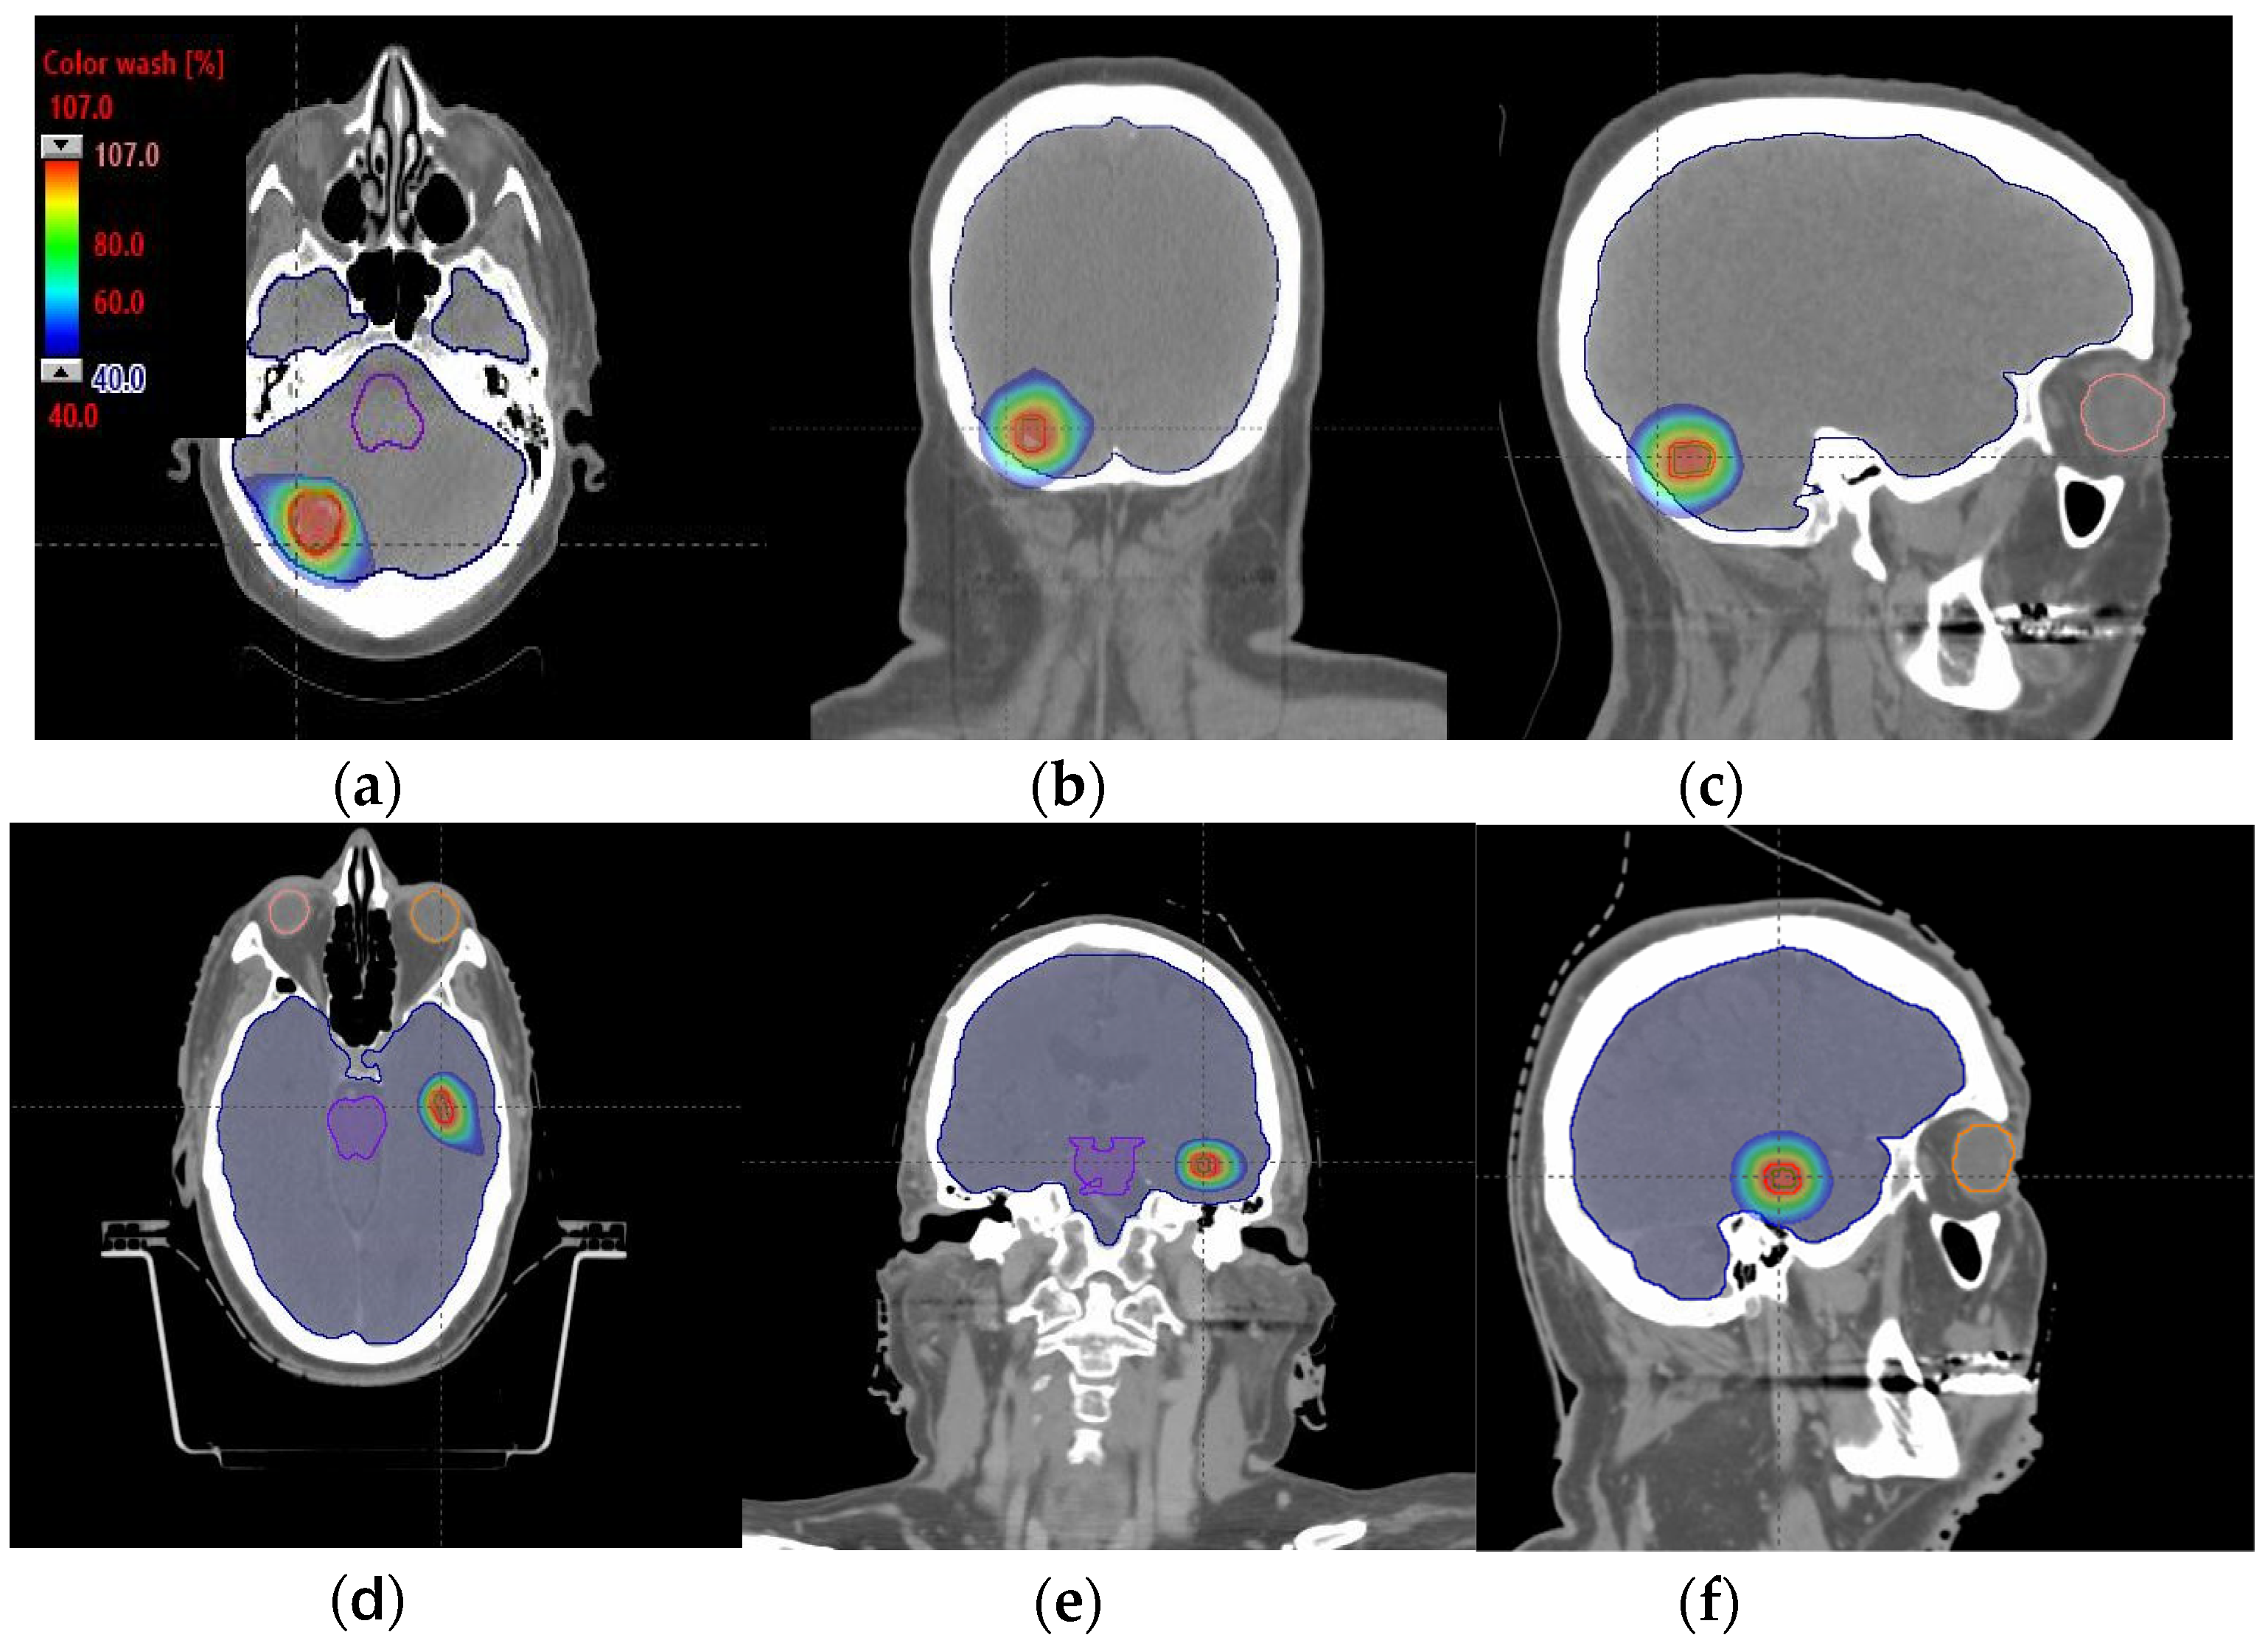

Figure 4.

Axial, coronal, and sagittal CT slices of brain patients 1 (a–c) and 2 (d–f). Dose distribution is displayed in both patients, including isodoses from 40% (blue) to 107% (red) of the prescribed dose.

PTV coverage and homogeneity were found to be maintained using a 120 MeV compared to high-energy MIBE (Table 1). In these tables, green values correspond to values that fulfill the clinical dosimetric requirements for a specific volume. Orange values indicate values within ±2% of the dosimetric goals, and red values indicate deviations greater than ±2% from the objective values. Dose sparing in OARs for a 120 MeV MIBE was remarkable compared with the other energies employed (Table 1). DHVs for the developed plans in each patient are displayed in Figure 3a,b. Representative axial, sagittal, and coronal CT slices with overlayed isodose distributions are shown in Figure 4a–f for the plan with the lowest MIBE that satisfied the clinical goals for each of the assessed patients. In both cases, we used a 120 MeV MIBE value. For the 120 MeV and 160 MeV MIBE values, some fields were found not to contribute to dose distribution as the beam range was insufficient to reach the target voxels. For patient 1, the gantry angle range started from 140 to 300 degrees for an MIBE of 120 MeV, and from 60 to 360 degrees for an MIBE of 160 MeV. For patient 2, this range covered values from 40 to 140 degrees for an MIBE of 120 MeV and from 340 to 180 degrees for an MIBE of 160 MeV. Note that all these arcs are defined in the clockwise (CW) direction.